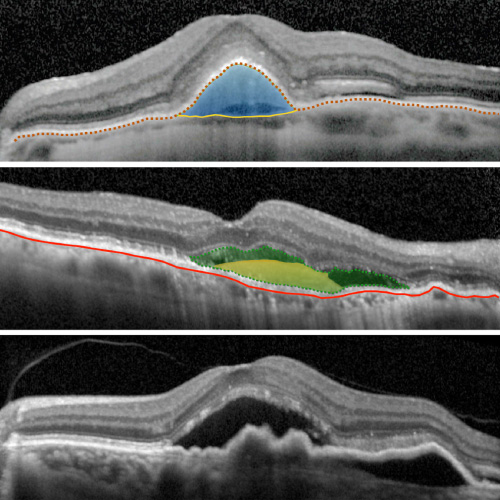

Analiza las alteraciones estructurales del Epitelio Pigmentario a nivel macular

Diagnostica el despegamiento de la neuroretina del Epitelio Pigmentario de la Retina

Estudia la pérdida de continuidad de la neuroretina en la mácula

Análisis del desprendimiento seroso de la retina en la mácula

Examina la superficie retinal y los cambios producidos por la interfase vitreoretinal

Evalua las alteraciones producido por efecto de las fuerzas de tracción de la interfase vitreoretinal